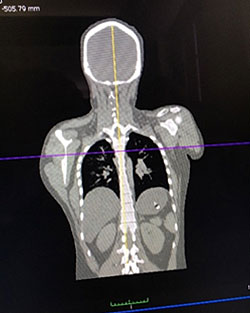

Exhibit 2. Three-Dimensional Scan and CT Scan

Three-Dimensional Scan and CT Scan

Source: Photos taken by Danielle McLeod-Henning (NIJ) at the University of New Mexico (2016).

The first image shows a three-dimensional rendering of a torso showing hip fractures. The second image is a computed tomography (CT) scan of a torso on a coronal plane. Both images were viewed through a program called OsiriX.